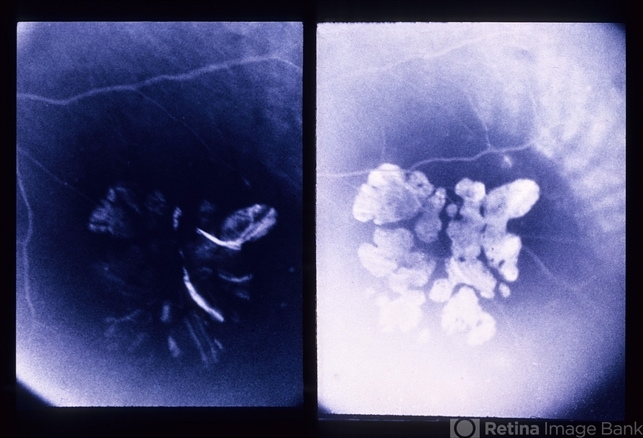

- retinal pigment epithelium (RPE) hypertrophy

- FA of the same patient. Shows typical window defects in the lacunar area due to chorioretinal atrophy #2.